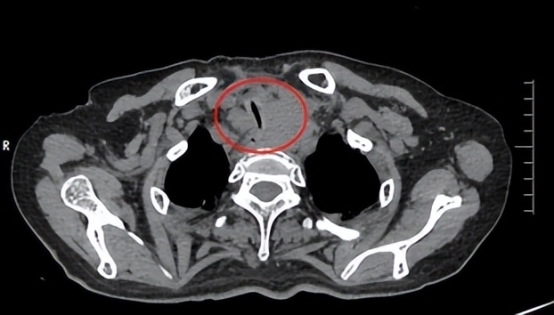

手术使用硬质气管镜快速建立生命通道,为后续操作创造了必要的空间。超细支气管镜深入狭窄段,准确定位支架释放区域。将镍钛合金网状支架精准展开,瞬间撑开了“塌陷隧道”,恢复了气道的通畅。

18:59:硬镜成功突破狭窄段,患者的血氧饱和度迅速回升至99%。

19:10:支架成功释放,气道直径恢复至8mm,患者的呼吸状况得到明显改善。

(术中)